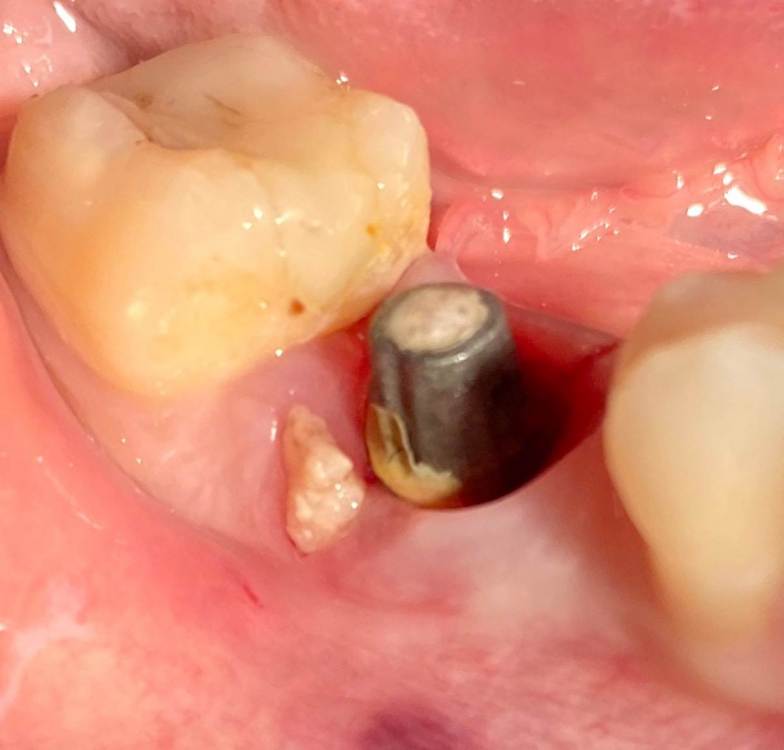

колесников Опубликовано 5 июля, 2022 Поделиться Опубликовано 5 июля, 2022 Здравствуйте коллеги. Год назад попалась публикация где описывался случай как ксеноаугментат секвестрировался спустя 12лет. Мне на днях попался аналогичный случай. Спустя 5 лет(графт bio-oss). Пусковым механизмом, вероятно ,был цемент ,попавший в придесневую шахту после фиксации. Ещё из интересного: интегрированный имплант (mis)удалён ключом на реверс. Вывод: чистый ксено-это не кость. 6 Ссылка на комментарий

АнтонТЛТ Опубликовано 6 июля, 2022 Поделиться Опубликовано 6 июля, 2022 Израильские имплантаты с шестигранником все легко удаляются ключом на реверсе. Ортопед красавчик, не пожалел цемента. 1 2 Ссылка на комментарий